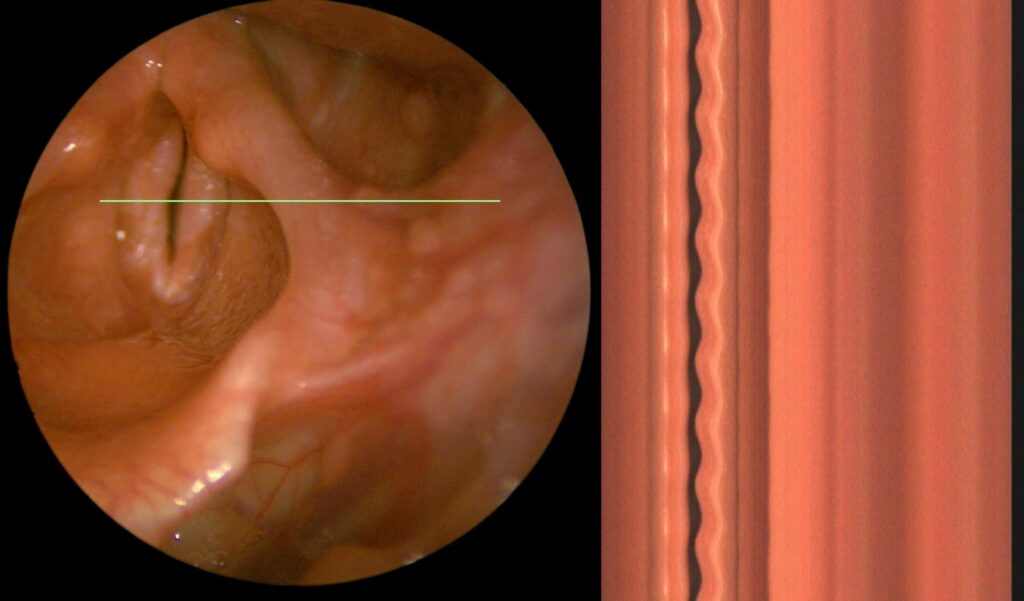

The visual information provided to the physician consists of two parts. The first part is an overview image used for navigation on the vocal cords and to indicate the specific location on the vocal cords from which the kymogram is obtained. The second part is the kymogram itself. A kymogram is therefore visual data from a high-speed camera, in our case 6500 frames per second, where an image corresponding to the area below the green line on the overview image is superimposed. So, essentially, 6500 times per second, we look at what is happening below the green line, and for greater clarity, we display all these image segments from the area below the green line one below the other.

On a kymogram, the doctor can observe whether both vocal cords are vibrating, whether the amplitude is the same, how large it is, how long the vocal cords remain open compared to the duration of closure, and whether the vocal cords close completely at all. They can observe the symmetry of the vibration, the phase shift of the vibration, how long a single vibration lasts, and how this duration changes. Advanced features suitable for observation include the sharpness of the peaks—both medial and lateral—as well as various aberrations.